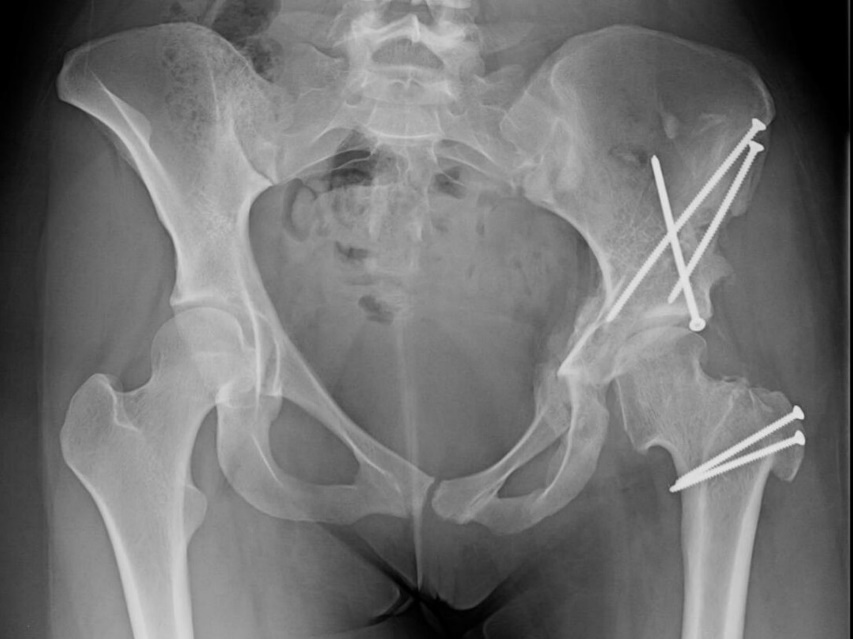

Left hip dysplasia with femoral head subluxation

Left hip dysplasia with femoral head subluxation.